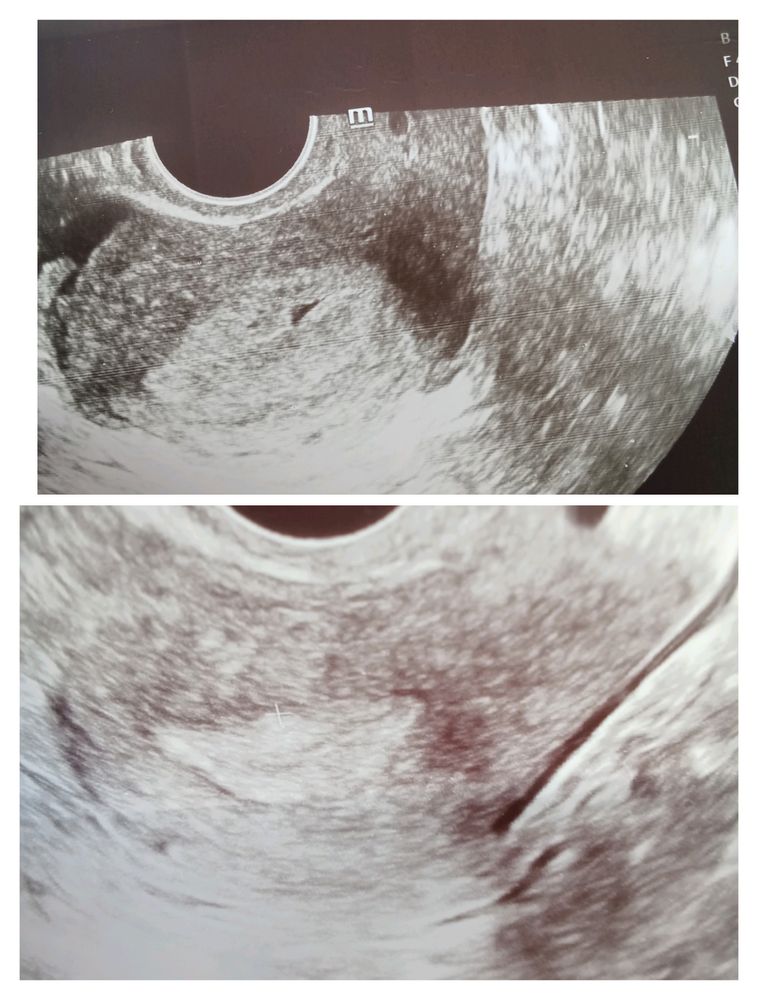

Мама индахаус, вот какая то полость появилась. Врач побоялась делать прогноз. Сказала через неделю посмотрим. Вот сравнение УЗИ июля и сегодня. Не было такого. И эндометрий такой впервые.обычно 12-14. В бхб было 16. А тут средняя величина 18. Изображение

AnTyumen, Изображение